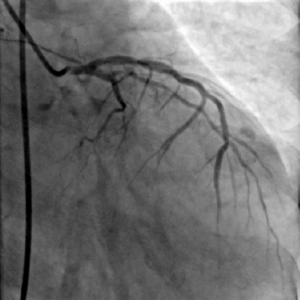

冠脉造影

LAD可见:近段70%-80%弥漫性狭窄,远段75%局限性狭窄,向右冠发出极丰富倒枝循环

LCX远段闭塞

右冠中段闭塞

冠脉造影提示患者存在严重冠脉病变,结合病史,缺血性心肌病诊断明确;

CAG后即刻出现血压下降、心率增快,考虑循环崩溃,因此需立即解决重度主动脉瓣狭窄